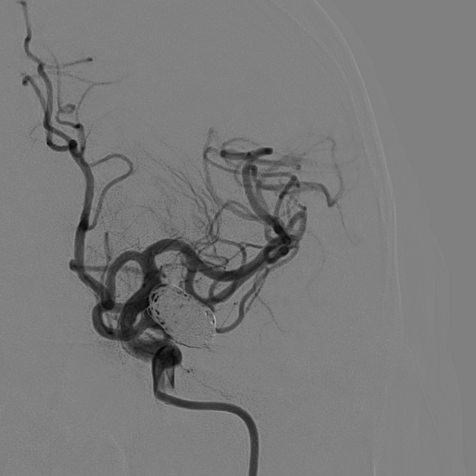

填圈、成篮。

直接释放支架,展开良好,完全覆盖瘤颈。

换至填圈角度,继续填圈。

填塞满意,同时将微导管退出瘤颈,并解脱。

换至释放支架角度,见瘤颈处少许残留,用弹簧圈输送钢丝将微导管再次置入瘤颈,填入弹簧圈2mm/4cm一枚。

术毕,填塞满意。

动脉瘤填塞满意。

支架展开、贴壁良好,分支血管通畅。

支架导管、微导管到位,通桥银蛇®DA远端通路导引导管稳定支撑。

支架半释放;继续填圈;通桥银蛇®DA远端通路导引导管稳定支撑,术毕。

动脉瘤填塞满意;支架展开良好。